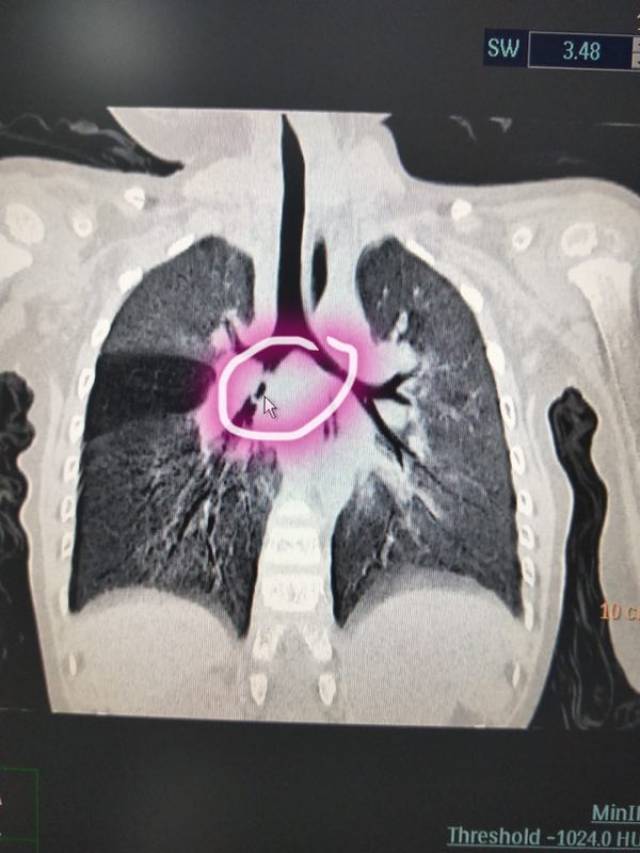

先看影像学检查:胸片,ct,看到了左主支气管内异物以及阻塞性肺不张.

经胸部ct和气道三维重建检查,结果也提示有异物,我们建议做气管